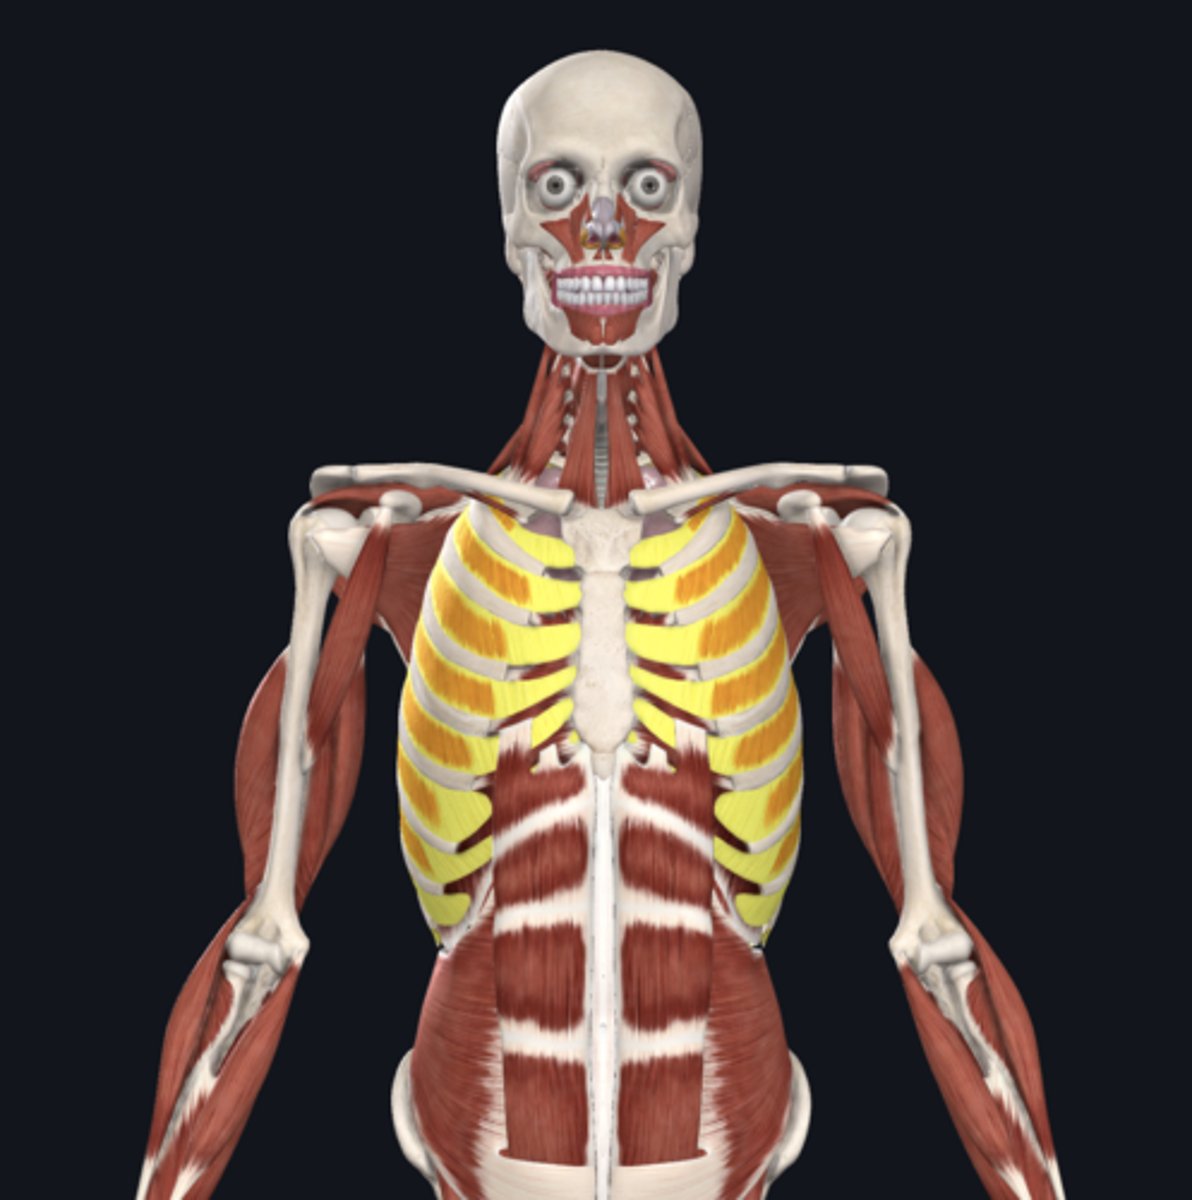

diaphragm

anterior scalene

middle scalene

posterior scalene

intercostal muscles

pleural sac